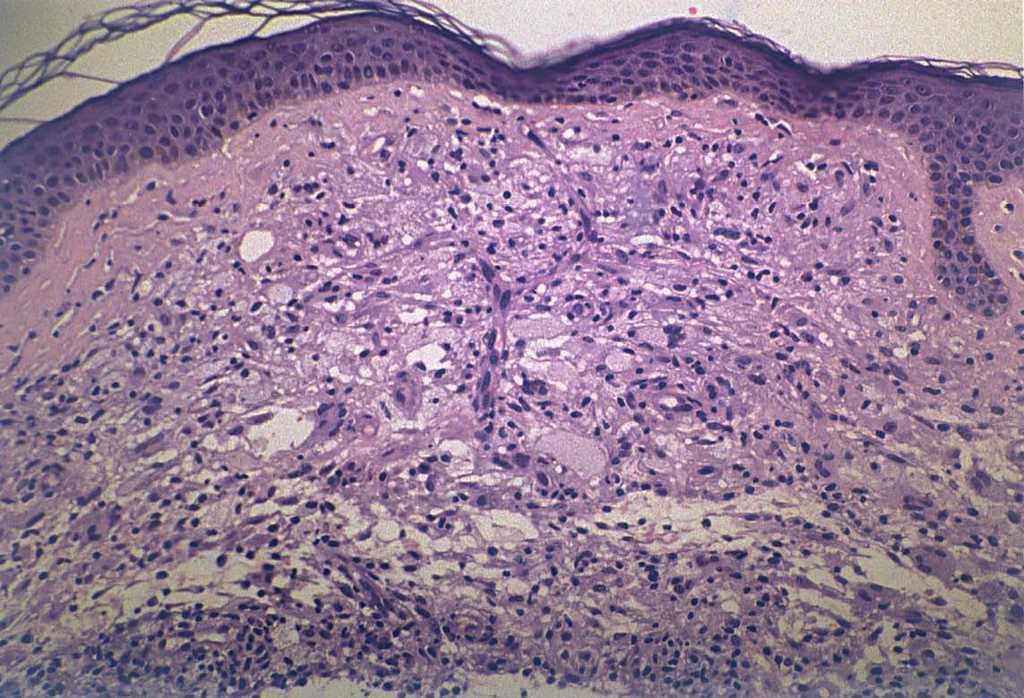

El hemograma y la bioquímica, incluyendo los niveles de colesterol y triglicéridos, fueron normales. Se realizó biopsia cutánea de una de las lesiones de la espalda (fig. 3).

Fig. 3.—Infiltrado difuso de histiocitos espumosos en dermis acompañado de alguna célula gigante multinucleada. (Hematoxilina-eosi-na, ×40.)

En el examen histopatológico se observó un infiltrado difuso de histiocitos espumosos en dermis superficial y media acompañado de alguna célula gigante multinucleada (fig. 3).

El xantoma plano difuso es una entidad clinicopatológica bien definida, aunque poco frecuente, que se engloba dentro de las xantomatosis normolipémicas. Se caracteriza por la aparición lentamente progresiva de máculas o pápulas amarillo-anaranjadas, escasamente sobrelevadas, que confluyen en extensas placas que pueden ocupar gran parte de la superficie corporal. Son asintomáticas y normalmente comienzan como xantelasmas palpebrales que se van extendiendo a caras laterales de cuello y parte superior del tórax1-14 . Es frecuente la afectación de flexuras y cicatrices antiguas. También se ha descrito afectación de mucosas y, de forma excepcional, tendones y otros órganos5,6 . Es una enfermedad poco frecuente, con incidencia similar en ambos sexos y que por lo general afecta a individuos mayores de 50 años4,6 . En el estudio histológico se pueden observar acumulaciones de células xantomatosas grandes con núcleo central redondeado y con citoplasma espumoso, difusamente distribuidas por la dermis junto a un moderado infiltrado inflamatorio constituido por leucocitos y linfocitos. En ocasiones se encuentran células gigantes tipo Touton1-14 .